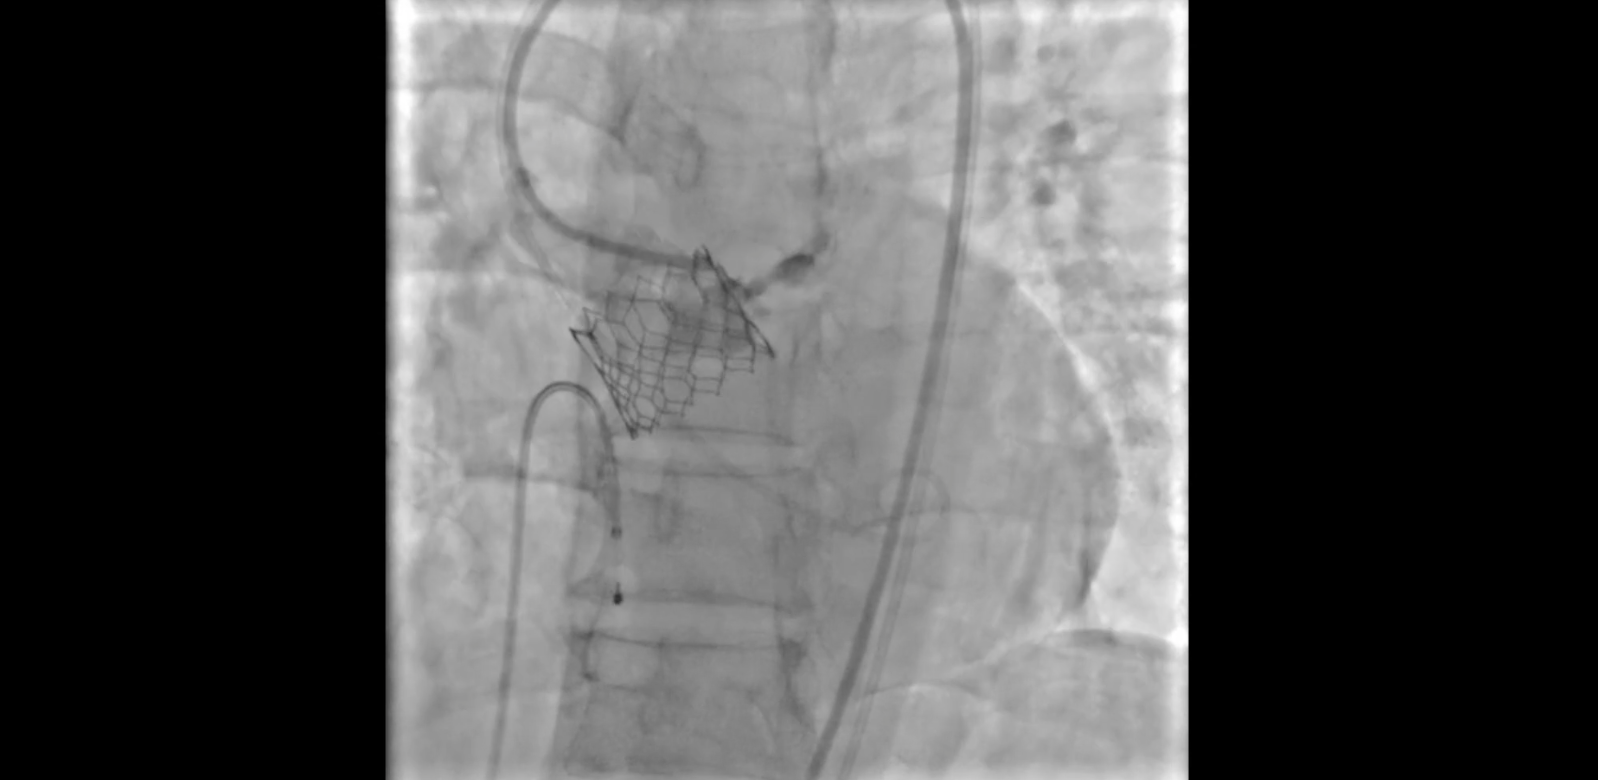

Percutaneous Approach With Coil Embolization for Annular Rupture During Coil Embolization For Rupture Web the use of coils for percutaneous vessel embolization was first reported by gianturco 6 who designed a. Web endovascular coil embolization is a percutaneous approach to treat an. Web embolization of brain aneurysms and arteriovenous malformations (avm) uses imaging guidance to place small, soft metal coils. Web since the introduction of guglielmi detachable coils (gdcs) in clinical neuroendovascular practice,. Coil Embolization For Rupture.